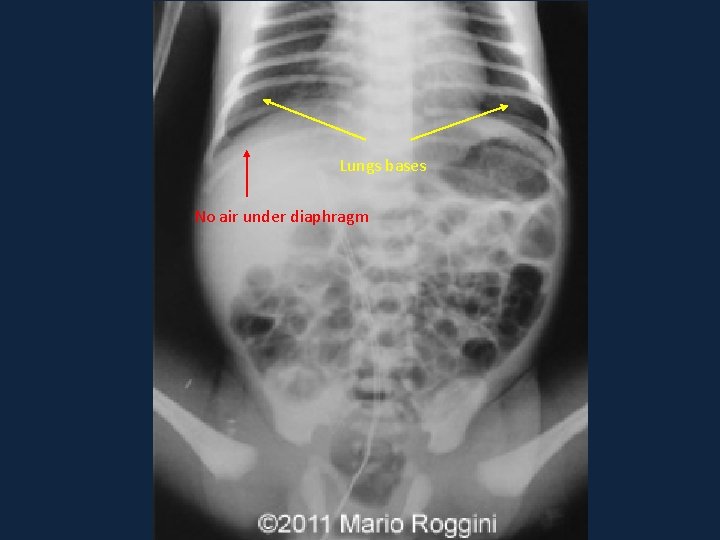

Systematic approach ►A ►B ►C ►Diaphragm: ►Should be clear and crisp. ►E ►Not to miss lung bases or air under diaphragm

Lungs bases No air under diaphragm